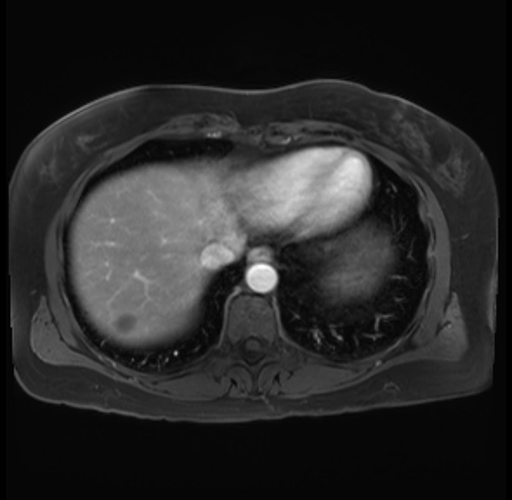

Imaging Analysis

Look through the patient's CT scan to identify any areas of concern for the necessary procedure.

Based on your CT findings, which issue(s) are present and would give reason for "planned slowing down moment(s)" in this case?